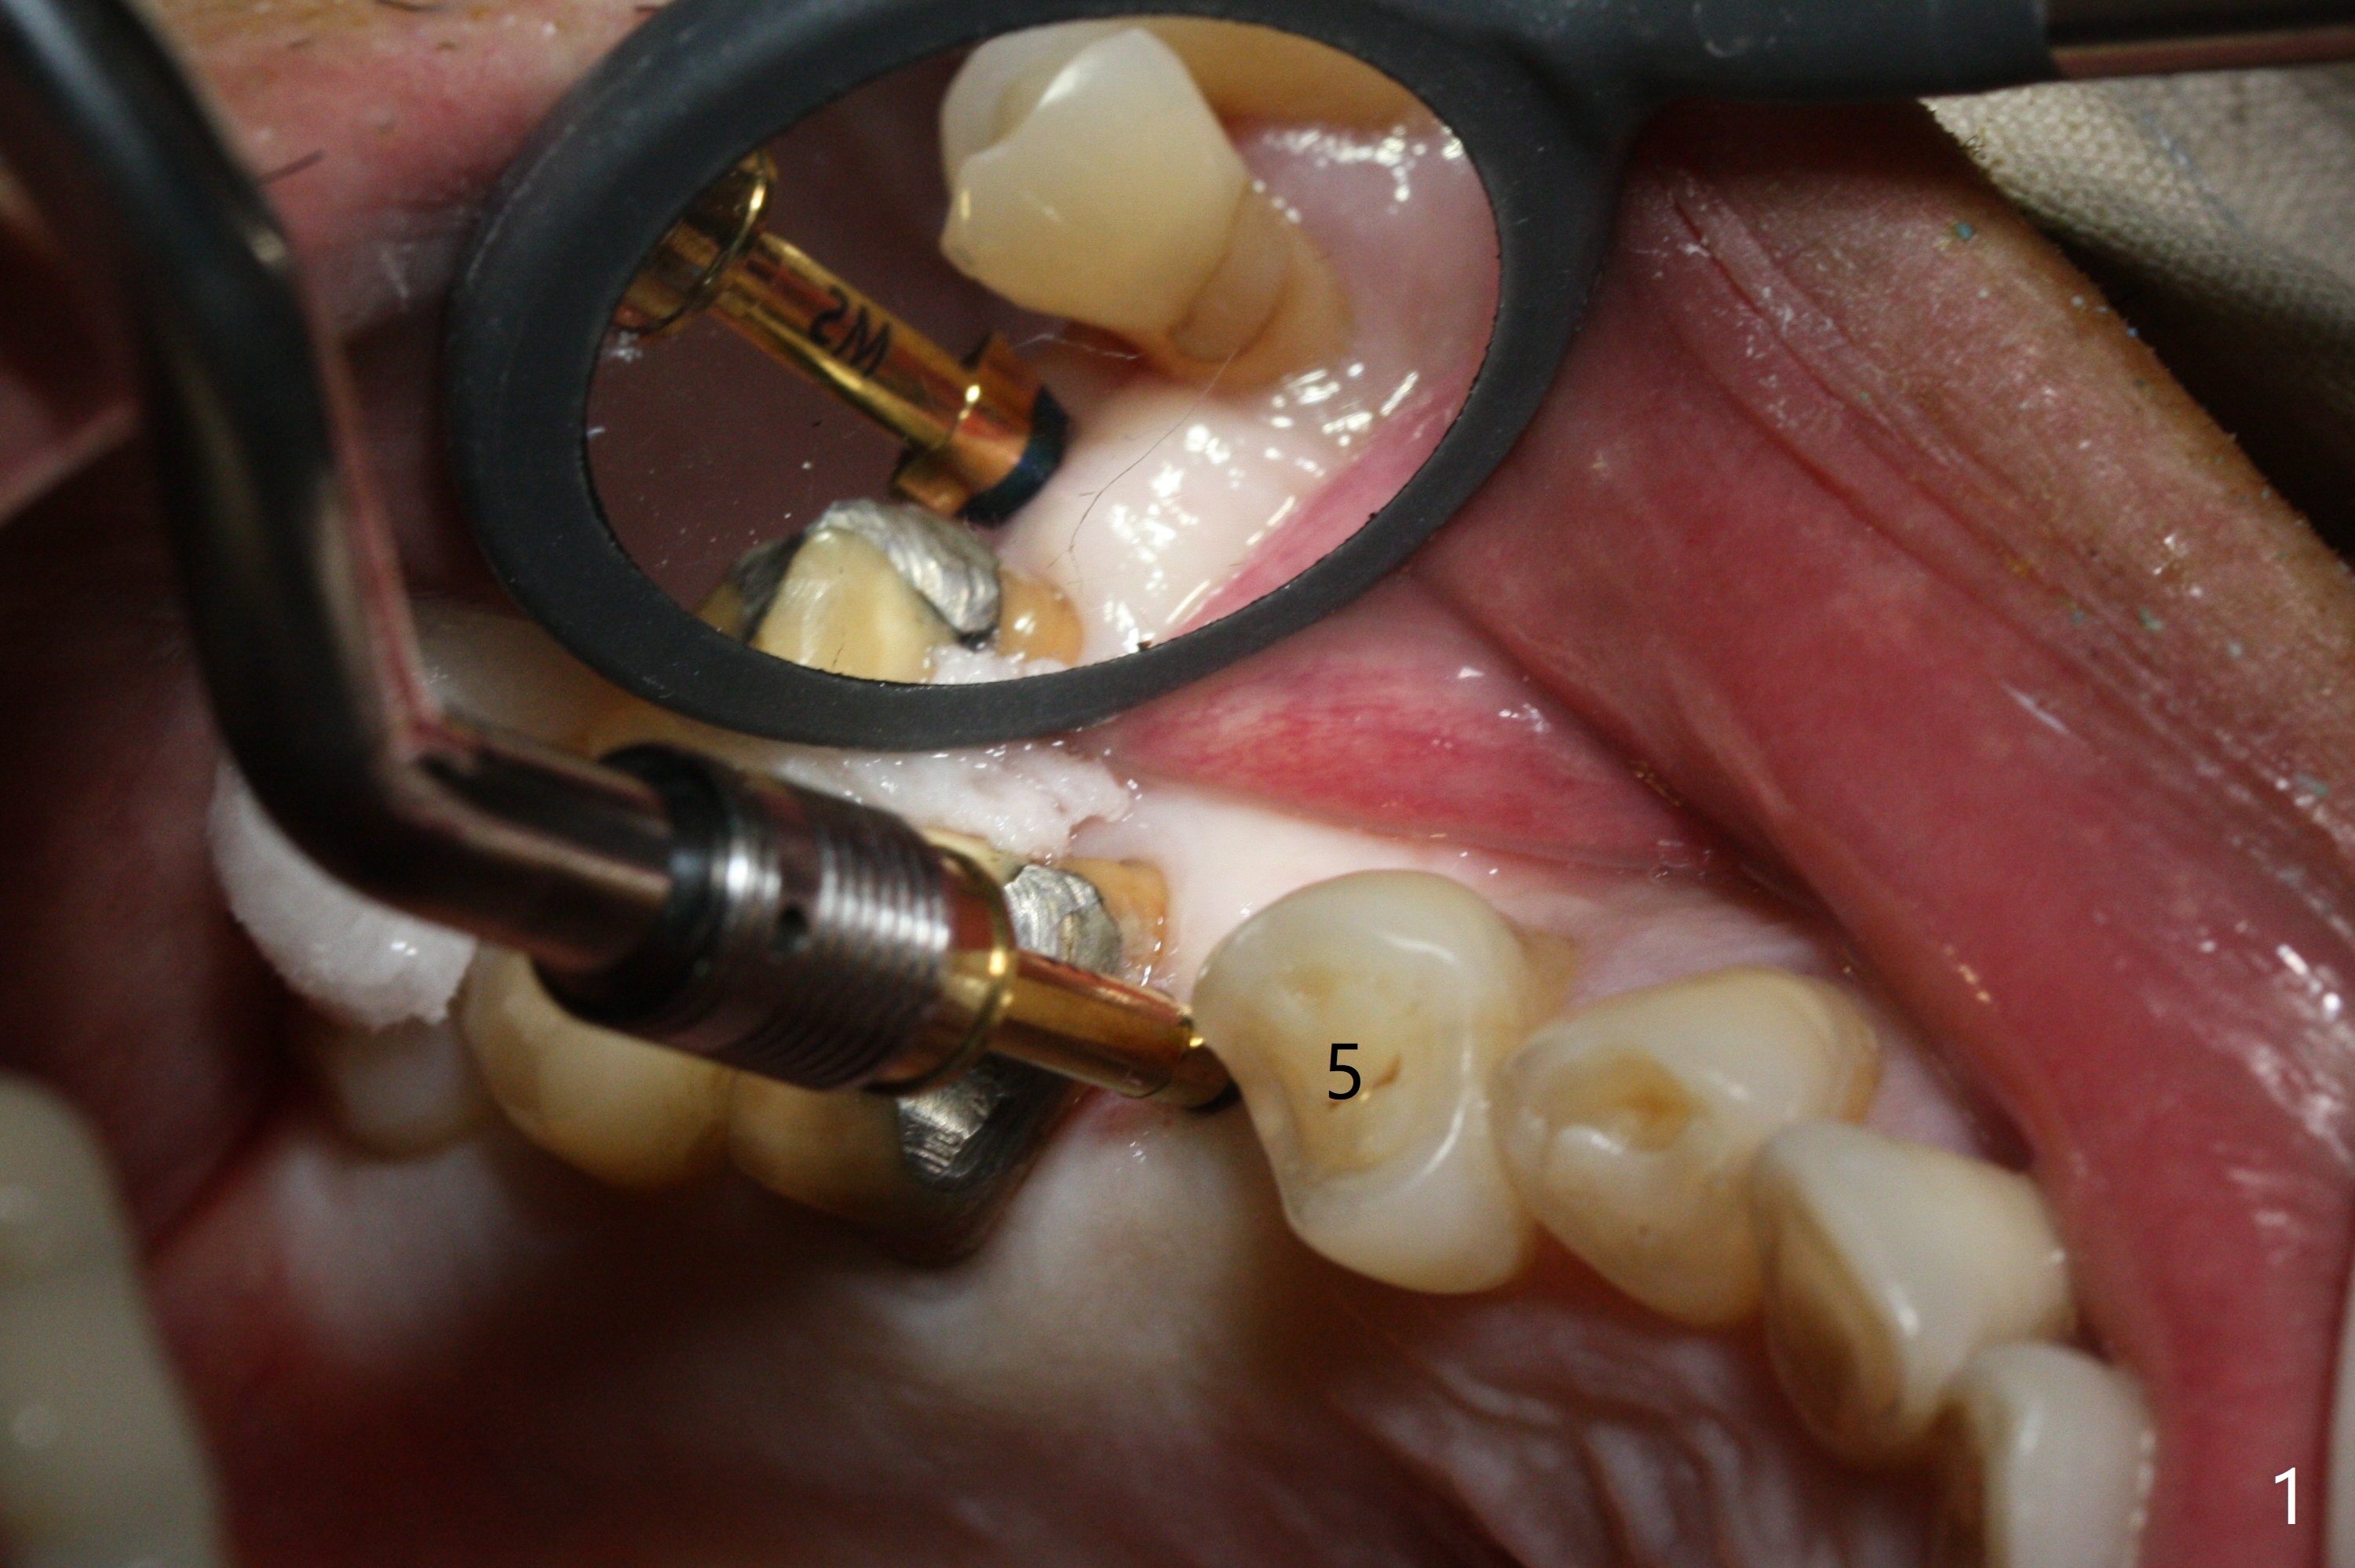

As planned, osteotomy starts at #4 prior to #3 extraction (Fig.1,2). In fact the bone density at the edentulous area is high. Drills are used to finish placing a 4x17 mm tissue-level implant (Fig.3).

A challenge associated with #3 extraction is large amount of granulation tissue apical to the mesiobuccal root (MB, Fig.2 (inset: red dashed line)). To remove the granulation tissue (*) apical to the septum (S), the septum between the buccal roots has to be chiseled. The remaining septum for osteotomy becomes less.